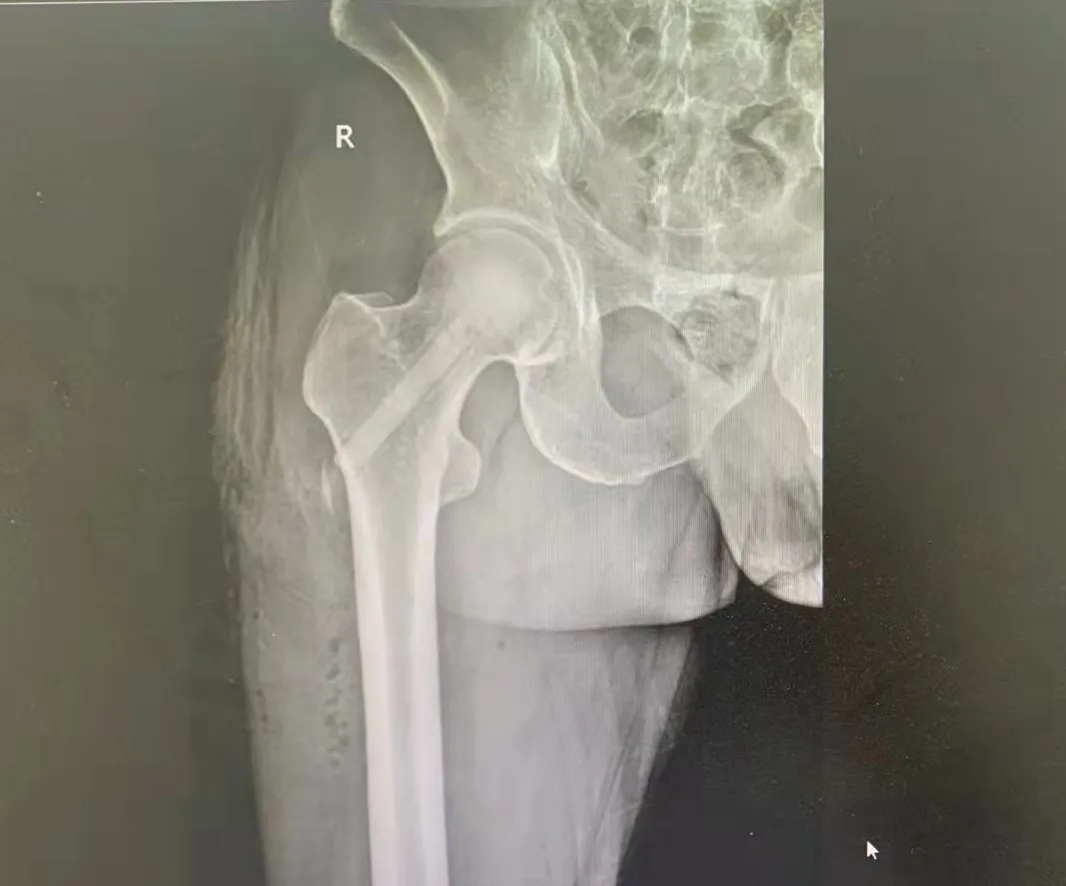

52歲的孟先生兩月前無(wú)明顯誘因出現(xiàn)右髖部疼痛,站立及行走時(shí)加重,休息后可緩解,呈緩慢加重趨勢(shì)。11月中旬曾于當(dāng)?shù)蒯t(yī)院檢查示“雙側(cè)股骨頭壞死”,未做治療。后情況愈發(fā)嚴(yán)重,蹲起時(shí)疼痛明顯,站立時(shí)間縮短,不可遠(yuǎn)距離行走,經(jīng)朋友介紹后急來(lái)華潤(rùn)醫(yī)療徐州市礦山醫(yī)院就診。

入院后,MRI示:雙側(cè)股骨頭缺血性壞死,右側(cè)股骨頭局部骨髓水腫。確診為雙側(cè)股骨頭無(wú)菌性壞死(Ficat—II期)。骨科專(zhuān)業(yè)技術(shù)主任李先啟、骨二科副主任顧署光及其團(tuán)隊(duì)經(jīng)過(guò)研究及討論,并與家屬協(xié)商后決定進(jìn)行保頭治療,手術(shù)后既可以避免人工關(guān)節(jié)置換,而取得一勞永逸的長(zhǎng)期效果。

術(shù)前影像